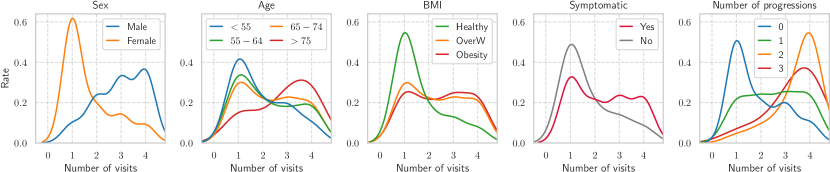

Finally, we also analyzed the frequency of follow-up decisions over 4 years in various subgroups split based on sex, age, BMI, symptomatic status, and the ground-truth number of progressions. The results were drawn from the experiment mentioned in Section 4.2 and displayed in Figure 9. Specifically, every participant, irrespective of their subcategory, had at least one follow-up, which is consistent with Figure 9. However, we observed that males were more likely to have additional visits compared to females. In terms of BMI, participants classified as overweight or obese obtained a higher number of follow-ups compared to those with a healthy BMI. When considering symptomatic status, our policy selected more follow-up decisions for symptomatic patients than asymptomatic ones, indicating its responsiveness to symptom presence. Age-wise, the number of recommended follow-ups increased towards older participant groups, being the largest for the ones over years old. When we compared the frequency of visits to the actual number of progressions, we found that participants with multi-progression were most likely to have frequent visits ( times).